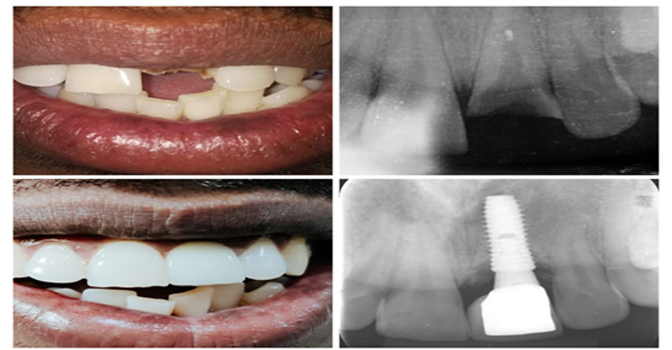

1) Single Tooth Implant

If you have a single missing tooth, whether due to carious damage or extraction, your dentist will place a single implant into the jawbone at the site of the missing tooth.

The implant will then undergo a bonding process with the surrounding tissue and bone, which typically takes a specific period. Once successful integration between the implant and the bone is achieved, a crown will be placed on top of the implant. This crown will effectively replace the visible portion of the lost tooth, ensuring a natural and aesthetically pleasing appearance.

The implant will then undergo a bonding process with the surrounding tissue and bone, which typically takes a specific period. Once successful integration between the implant and the bone is achieved, a crown will be placed on top of the implant. This crown will effectively replace the visible portion of the lost tooth, ensuring a natural and aesthetically pleasing appearance.